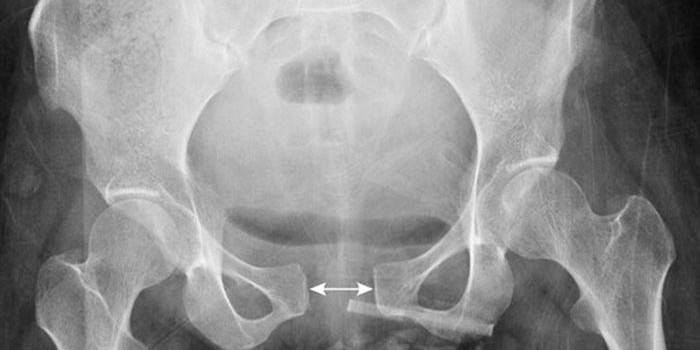

Grados

La sinfisitis puede tener diversas formas de gravedad, dependiendo de qué tan fuerte sea el ablandamiento, cómo se hayan dispersado los huesos conectados por la sínfisis. La segunda y tercera etapa de la enfermedad son indicaciones para una cesárea, que es realizada por el médico, y el parto natural es posible con sinfisitis durante el embarazo, si la discrepancia no es mayor de 1 cm y el niño es pequeño. Considere cuáles son las etapas de la enfermedad durante la gestación:

- etapa uno: una discrepancia de 5 a 9 milímetros;

- etapa dos: de 10 a 19 milímetros;

- Etapa tres: más de 20 milímetros.

- Ultrasonido del pubis: para identificar la etapa de la enfermedad en una mujer.

Este diagnóstico es una razón seria para la elección consciente del método apropiado de parto.Si la paciente cumple con todos los requisitos necesarios y la discrepancia no supera los 1 cm, es posible un parto natural. Pero al mismo tiempo, antes de las 37 semanas, no se puede elegir el método, porque para esto, a las 38-39 semanas, el especialista debe evaluar la condición del cartílago y tomar una radiografía. Si la discrepancia es pequeña y no hay otras contraindicaciones para el método natural, será elegido. Después del nacimiento, se restaura la condición de los huesos pélvicos.